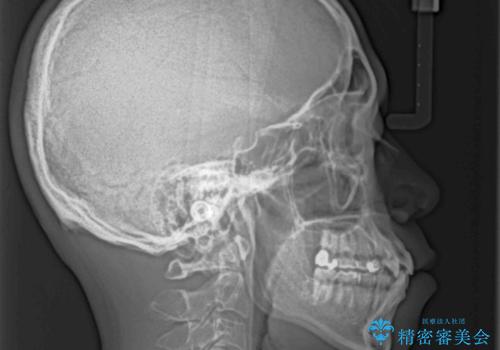

上下の前歯部に強い叢生(ガタガタの歯並び)があり、そのまま歯を並べると出っ歯になってしまう可能性がありました。

そこで、上下左右の第一小臼歯を抜歯し、歯が並ぶためのスペースを確保し叢生を解消する治療計画を立てました。

八重歯はきれいに整い、前歯もバランスよく収まり、横顔のラインも自然に改善されました。